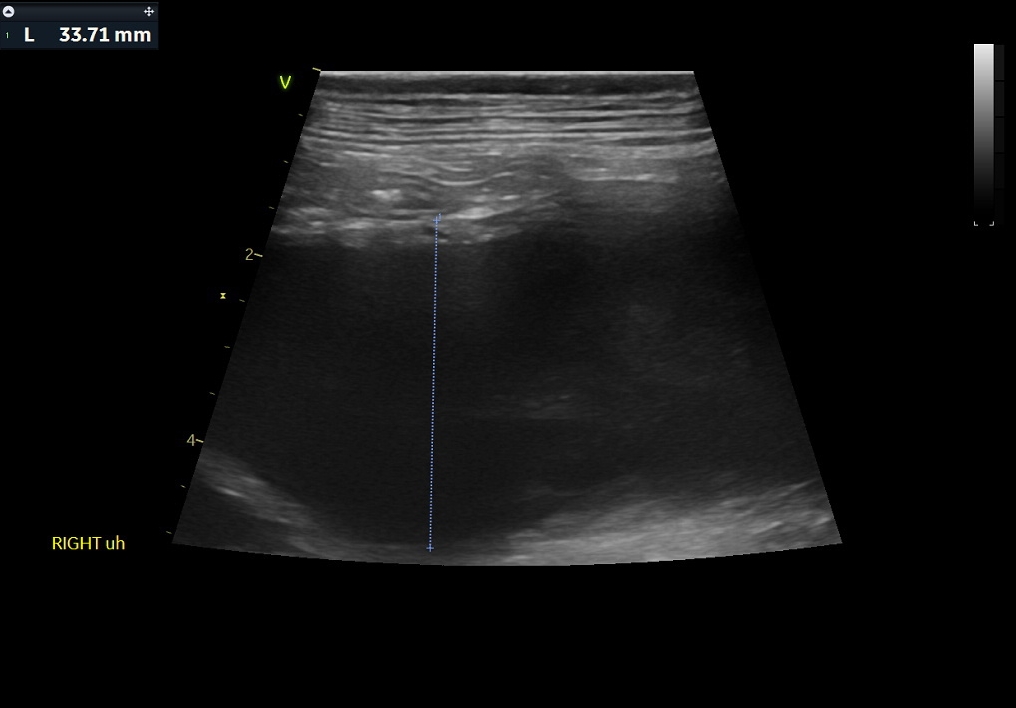

복부초음파 결과 / 출처: 24시온숲동물의료센터

복부초음파·방사선검사 결과

- 내원 당시 시행한 복부 초음파 및 방사선 검사에서 정상적으로는 4mm 정도 두께인 자궁이 약 4cm까지 심하게 확장되어 있는 모습이 확인되었습니다. 내부에는 고름으로 추정되는 내용물이 가득 차 있었으며, 이는 전형적인 자궁축농증의 소견에 해당합니다.